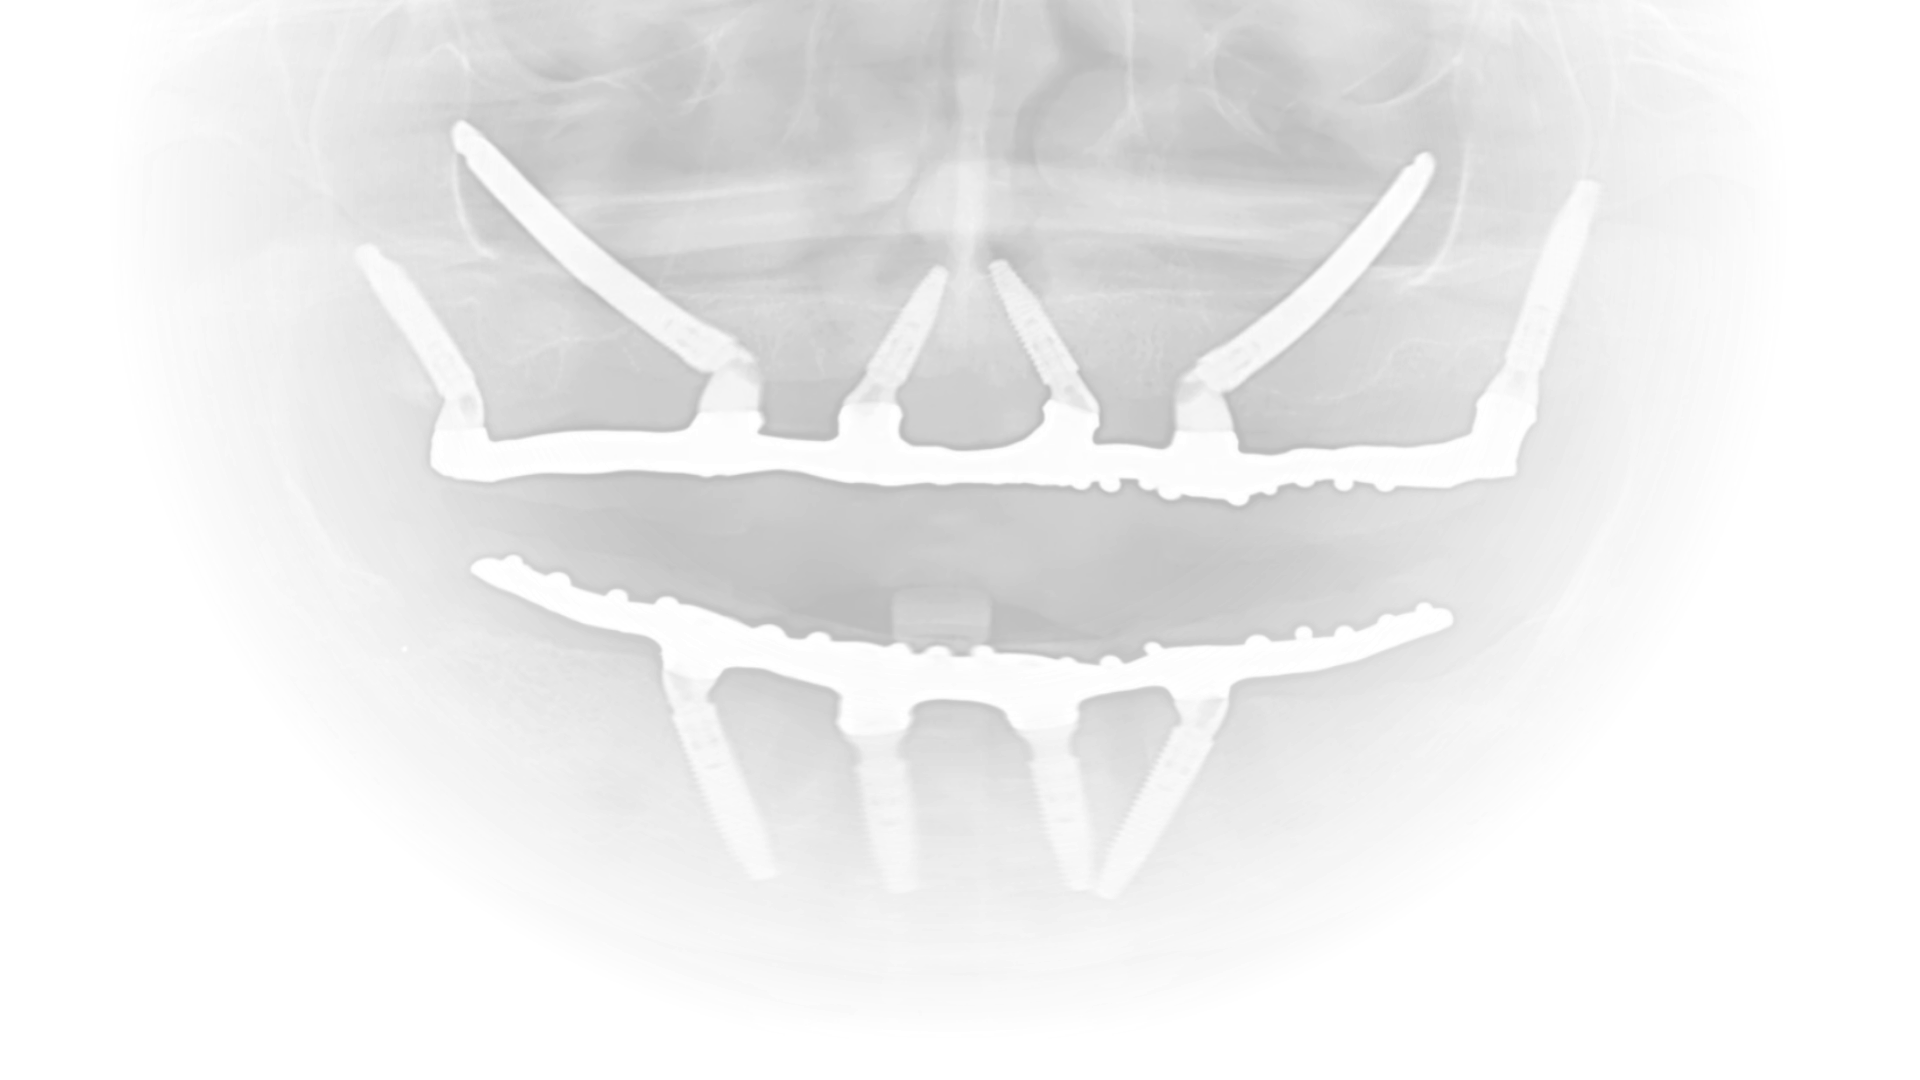

A ZYGO atua em parceria com dentistas que necessitam de suporte em casos de maxilas atróficas e reabilitações complexas. Com a expertise do Dr. Caio Miranda e do Dr. Felipe Antunes, nossa clínica realiza procedimentos de alta complexidade, como implantes zigomáticos com carga imediata, garantindo:

Previsibilidade e planejamento cuidadoso.

Segurança cirúrgica e pós-operatória.

Qualidade clínica e estética nos resultados.